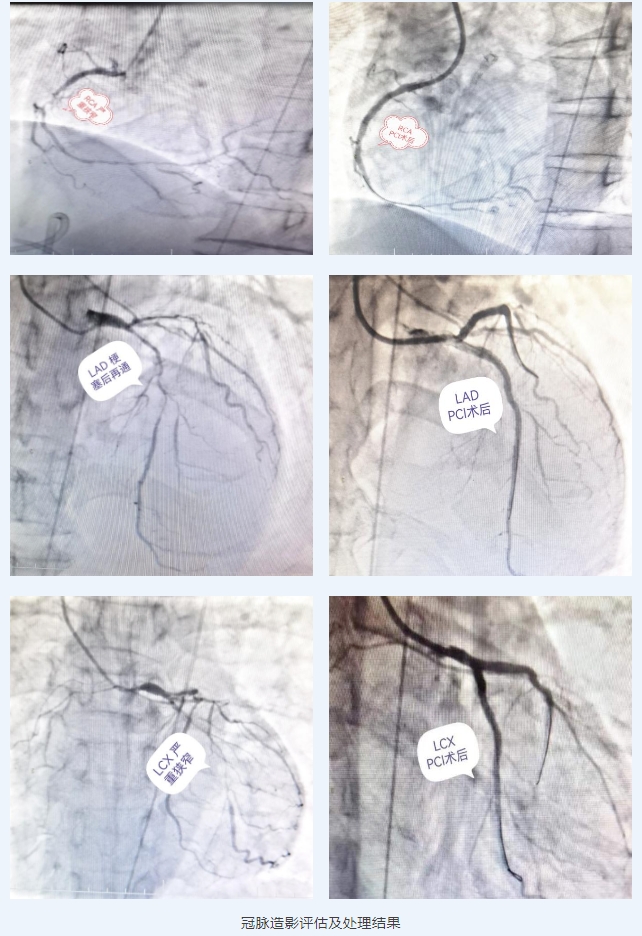

患者李先生(化名),因反复胸闷痛3周,加重2周,拟急性心肌梗死入院,立即送介入室行冠脉造影,前降支近中段狭窄90%,回旋支狭窄90%,右冠过第一道弯后最重,狭窄约95%%,立即行PCI,迅速开通病变冠脉。急性心肌梗死后,二尖瓣腱索断裂脱垂并重度关闭不全,二尖瓣极重度反流,外科会诊考虑患者心功能NYHAIV级,冠脉支架植入术后行外科手术风险大。经过详尽的检查,食道超声提示患者1区后叶脱垂累及外交界,2区前叶脱垂,后叶栓系,病情相对复杂。尹秋林团队经多次仔细评估,经过心血管外科、超声科、麻醉科、导管室及护理团队等多学科讨论后,决定为患者行经导管二尖瓣钳夹术。屋漏偏逢连夜雨,手术日期已定,患者术前突发消化道出血,病情急剧反转,增加了二尖瓣钳夹术的风险,尹秋林团队时刻关注病情变化,密切观察指标变化,在医护患三者的共同努力下,患者消化道出血情况得到好转,经评估后,再次进行详细的讨论,制定方案,手术终于如期进行。

急性心肌梗死合并腱索断裂引起二尖瓣大量反流是急性心肌梗死的严重并发症,其可导致严重肺水肿及心源性休克,院内急性期死亡率可高达70-80%。外科手术对于此类患者的手术风险极高。此例患者系回旋支远端闭塞,引起后乳头肌缺血导致乳头肌、腱索断裂,二尖瓣重度反流。虽然目前患者EF%尚可,但是急性二尖瓣重度反流引起的左心衰竭导致患者病情进行性恶化,左心房和左心室急剧扩大(LVD 67mm,LA 56mm),血流动力学不稳定,心源性休克。在成功植入两枚夹合器后,二尖瓣反流明显改善,术中收缩压即刻回升15-20mmHg,血流动力学平稳,即刻拔除IABP左室辅助装置,术后1周内复测床边超声(LVD 37mm,LA 44mm)。总体来说,针对危重患者,经导管二尖瓣钳夹术手术创伤小、恢复快,可明显改善二尖瓣反流,缓解心衰症状,改善生活质量,降低住院率和死亡率。